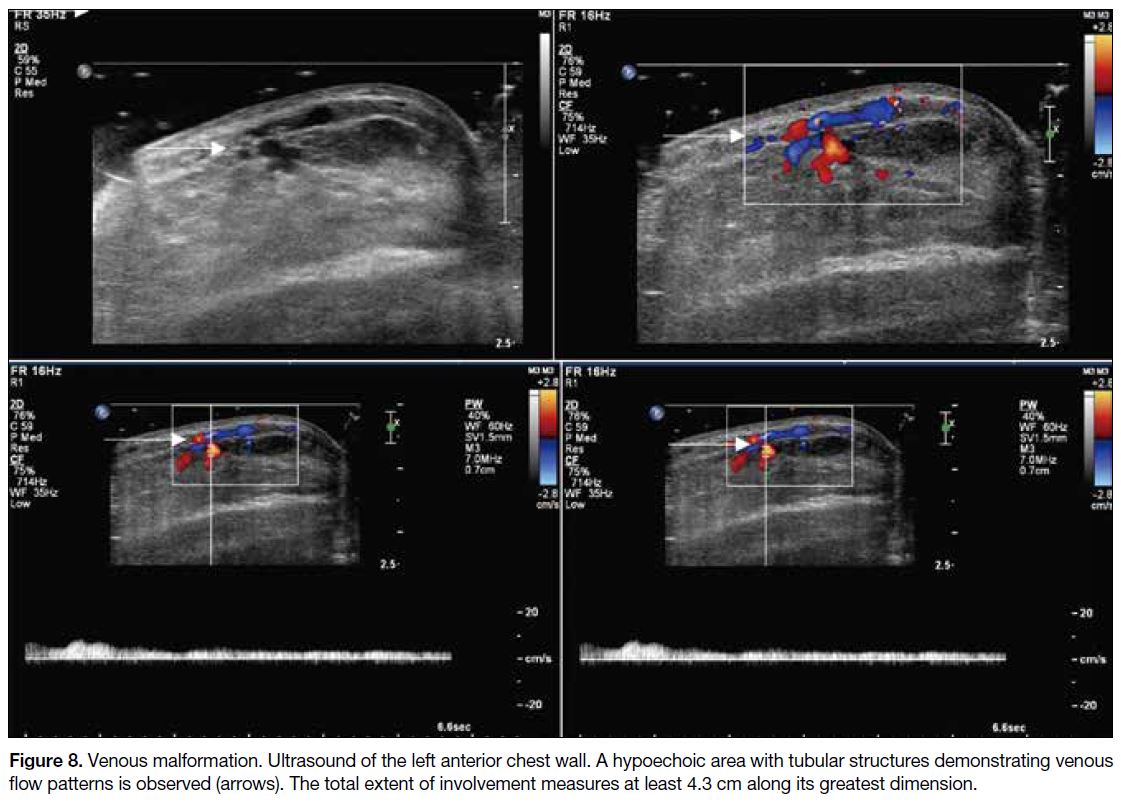

Ultrasound can be a good initial tool to establish the

diagnosis. These lesions are identified as an area of

hypoechogenicity within the breast. Doppler ultrasound

on this hypoechoic area will demonstrate the venous

flow pattern on spectral technique (Figure 8). Other

sonographic findings include echogenic foci indicating

phleboliths and absence of colour uptake due to

thrombosis or lymphatic components.[10]

Figure 8. Venous malformation. Ultrasound of the left anterior chest wall. A hypoechoic area with tubular structures demonstrating

venous flow patterns is observed (arrows). The total extent of involvement measures at least 4.3 cm along its greatest dimension.